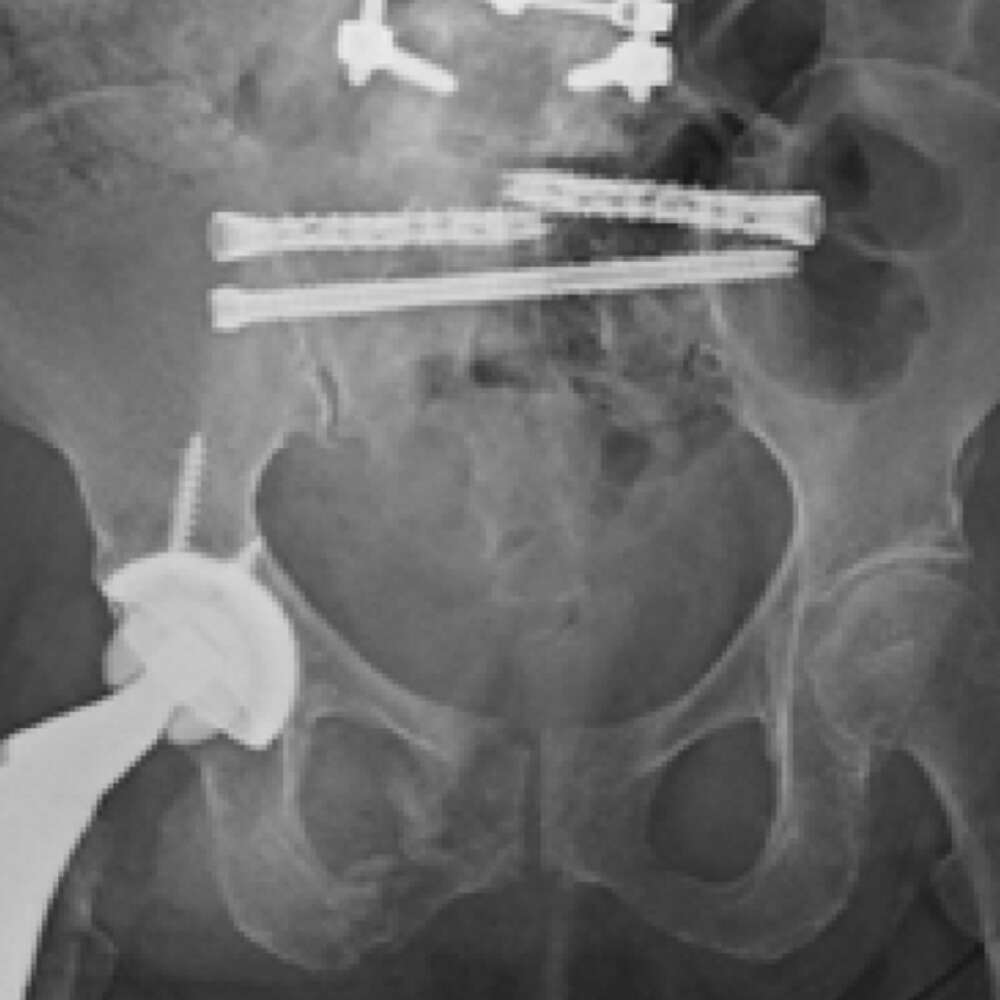

Sacral fracture fixation and bilateral SI joint fusion was performed.

- A single iFuse TORQ TNT™ implant was placed in the S2 corridor, spanning the sacrum and crossing both SI joints, addressing the left sacral alar nonunion and providing pelvic ring stability (Figs. 2-4).

- Percutaneous placement of bilateral iFuse TORQ® implants was performed sequentially, first at the left S1 and then the right S1, to provide additional sacral fracture fixation and to provide multiple fusion implants across the left and right SI joints.

Cunningham 1d